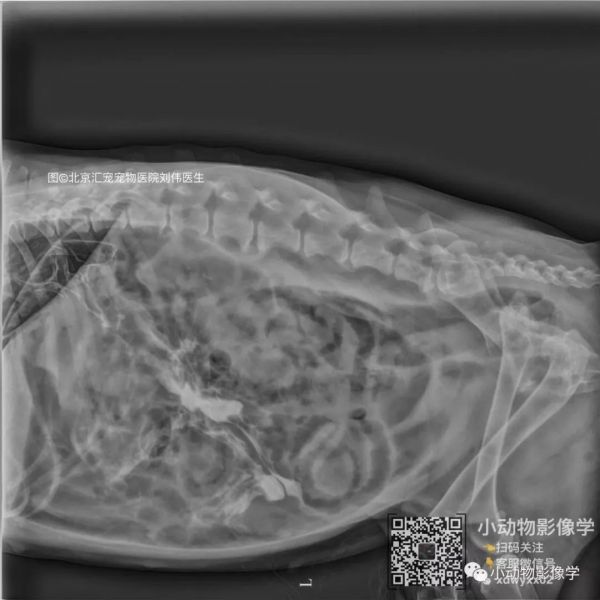

昨天(2018.12.26)小动物影像学客服微信小影和小影2号朋友圈发布了一个由刘伟医生提供的影像学案例,引起了热议。

动物信息和病史

松狮,13岁,前段时间得过胰腺炎。下午两点出现烦躁 ,四点进食后烦躁不安加重 ,呼吸急促 ,腹围增大。下面的影像依次为:刚来时(图1 图2)、抽气2L后(图3 图4)、造影后一小时拍的 (图5 图6)。病例由北京汇宠宠物医院刘伟医师提供。

影像所见

各肝叶间隙出现;腹腔各器官外边界出现;腹腔内壁清晰可见(由于气体衬托);膈是完好的受到后方压力膈向头侧突出;大量的气体不透明度出现在腹膜腔;胃肠道造影疑似造影剂漏入腹膜腔(但仍需后续确认)。

提示

考虑胃肠道穿孔引起的气腹(但仍需后续确认);其他引起气腹的可能仍未排除。